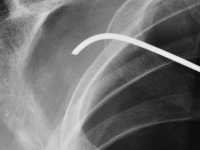

OtherForeign body ingestion is more common in children than in adults, but serious complications are less common in pediatric patients [1, 2]. Among adults, elderly individuals, those with masticatory disorders, esophageal strictures, prisoners, and patients with mental disorders predominate [2-4]. 80-90% of swallowed foreign bodies pass through the upper gastrointestinal tract spontaneously, but 10-20% require endoscopic removal, and 1% cause complications [3,5]. Possible locations of foreign bodies in the midpharynx include the epiglottis, the base of the tongue, the palatine tonsils, and in the hypopharynx, the piriform recesses, the retrocricoid region, and the posterior pharyngeal wall [6, 7]. In the esophagus, foreign bodies are located in the cervical part in over 80% of cases [1, 2, 8]. It is rare for a swallowed foreign body to penetrate the gastrointestinal tract and migrate deep into the soft tissues. This may be facilitated by the foreign body's structure, e.g., sharp-edged pieces of bone or glass. This poses a risk of serious and potentially fatal complications, such as retropharyngeal abscess, mediastinitis, or damage to the large vessels of the neck [7]. In such cases, prompt intervention and removal of the foreign body are essential. We present the case of a patient with a foreign body that migrated from the hypopharynx into the soft tissues of the neck, directly adjacent to the common carotid artery.